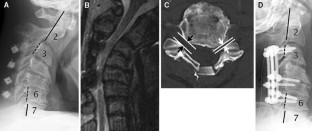

Though a possible cause of late neurological deficits after posterior cervical reconstruction surgery was reported to be an iatrogenic foraminal stenosis caused not by implant malposition but probably by posterior shift of the lateral mass induced by tightening screws and plates, its clinical features and pathomechanisms remain unclear. The aim of this retrospective clinical review was to investigate the clinical features of these neurological complications and to analyze the pathomechanisms by reviewing pre- and post-operative imaging studies. Among 227 patients who underwent cervical stabilization using cervical pedicle screws (CPSs), six patients who underwent correction of cervical kyphosis showed postoperative late neurological complications without any malposition of CPS (ND group). The clinical courses of the patients with deficits were reviewed from the medical records. Radiographic assessment of the sagittal alignment was conducted using lateral radiographs. The diameter of the neural foramen was measured on preoperative CT images. These results were compared with the other 14 patients who underwent correction of cervical kyphosis without late postoperative neurological complications (non-ND group). The six patients in the ND group showed no deficits in the immediate postoperative periods, but unilateral muscle weakness of the deltoid and biceps brachii occurred at 2.8 days postoperatively on average. Preoperative sagittal alignment of fusion area showed significant kyphosis in the ND group. The average of kyphosis correction in the ND was 17.6° per fused segment (range 9.7°–35.0°), and 4.5° (range 1.3°–10.0°) in the non-ND group. A statistically significant difference was observed in the degree of preoperative kyphosis and the correction angles at C4–5 between the two groups. The diameter of the C4–5 foramen on the side of deficits was significantly smaller than that of the opposite side in the ND group. Late postoperative neurological complications after correction of cervical kyphosis were highly associated with a large amount of kyphosis correction, which may lead foraminal stenosis and enhance posterior drift of the spinal cord. These factors may lead to both compression and traction of the nerves, which eventually cause late neurological deficits. To avoid such complications, excessive kyphosis correction should not be performed during posterior surgery to avoid significant posterior shift of the spinal cord and prophylactic foraminotomies are recommended if narrow neuroforamina were evident on preoperative CT images. Regardless of revision decompression or observation, the majority of this late neurological complication showed complete recovery over time.

Fig. 1